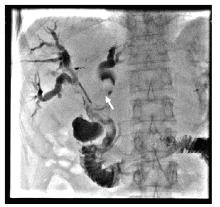

李勇:最终我们选择的治疗方案是胆道支架置入术联合碘125放射性粒子条治疗。如图3所示, 通过前期手术留置的PTCD引流管引入粒子条, 粒子条远端进入左肝管的一个主要分支、近端位于右肝管内; 从留置血管鞘应用双导丝引入一根超滑硬导丝, 沿硬导丝在左右肝管送入80 mm× 8 mm胆道支架一枚。利用支架膨胀张力使留置粒子条固定在胆道内, 然后引入导丝经已放置金属支架网眼进入胆总管、十二指肠, 建立轨道; 使用80 mm× 6 mm球囊扩张支架网眼后引入6F-Guide导管至胆总管中段, 沿导管送入一内装碘125的粒子条; 沿硬导丝在右肝管-胆总管送入80 mm× 8 mm胆道支架一枚。术后造影如图4所示。术前术后对比可以看到术后胆道情况明显好转。术后1个月复查CT(图5)示:与术前比, 肝内部分胆管轻度扩张, 以右叶为著, 左右肝管至胆总管下段内见支架植入, 支架内未见明显软组织影充填。